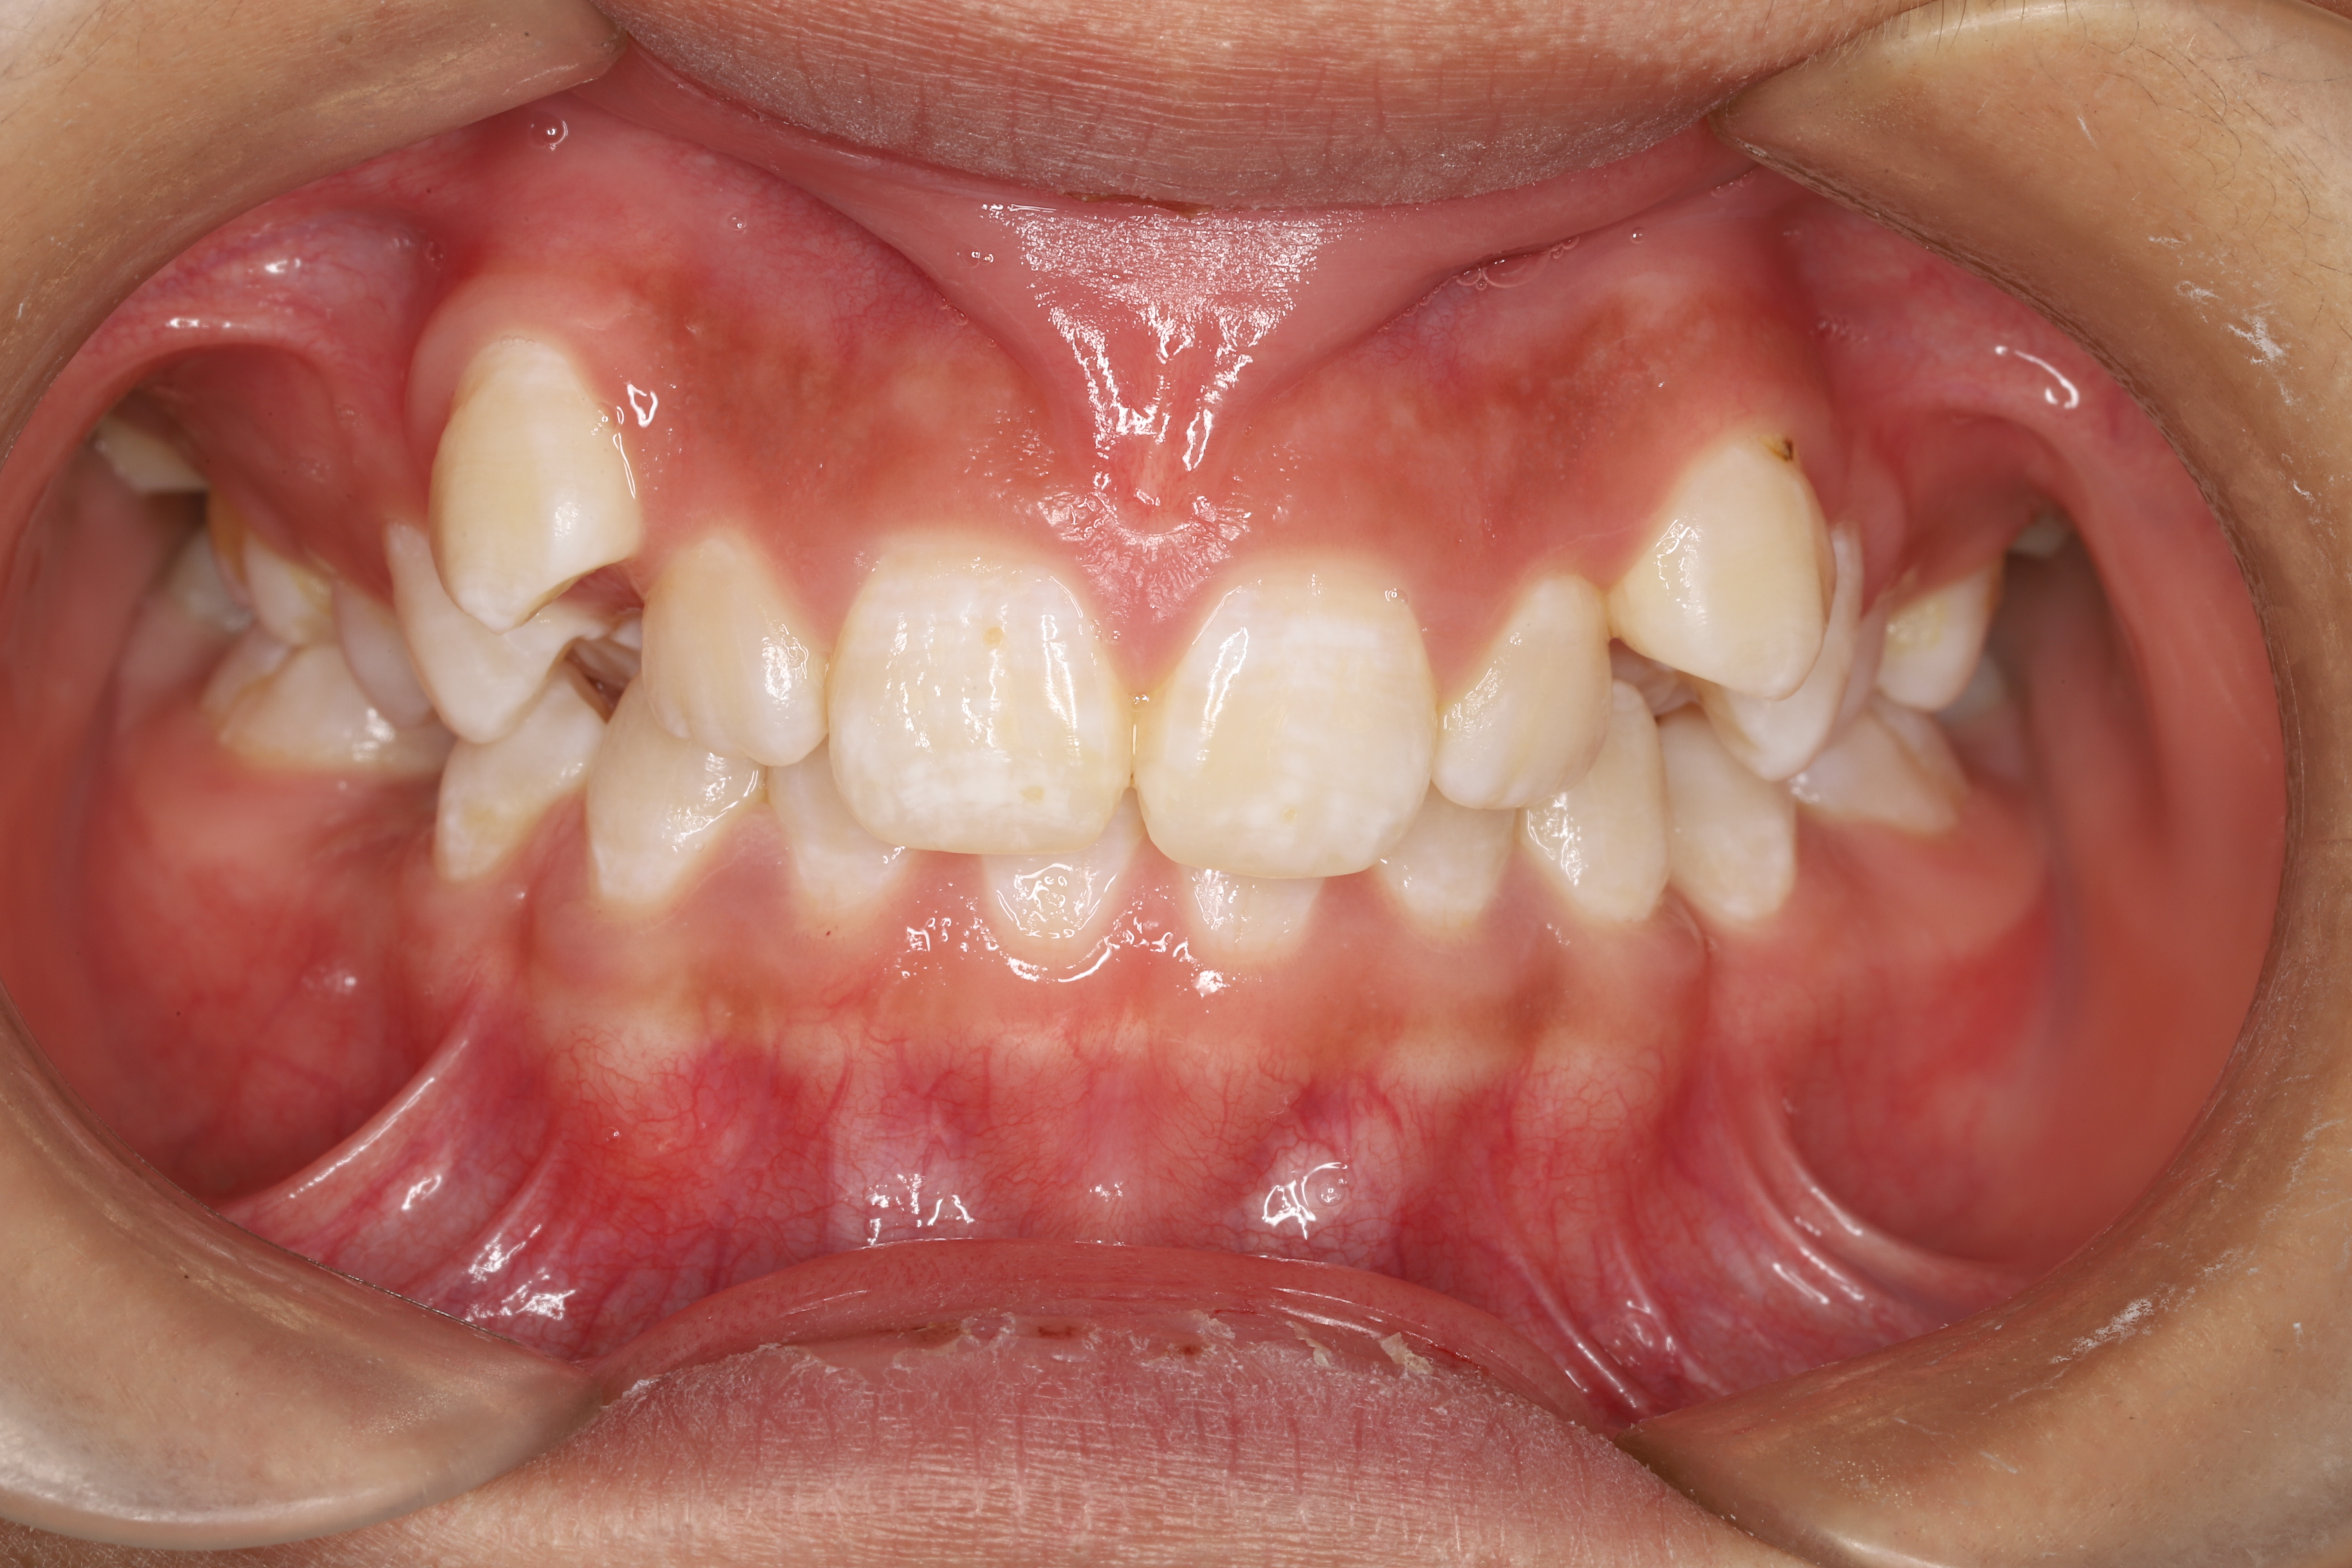

在回答这个问题之前,请看看下面几张图片。

关于儿童牙齿矫正那些事(图3)

开颌